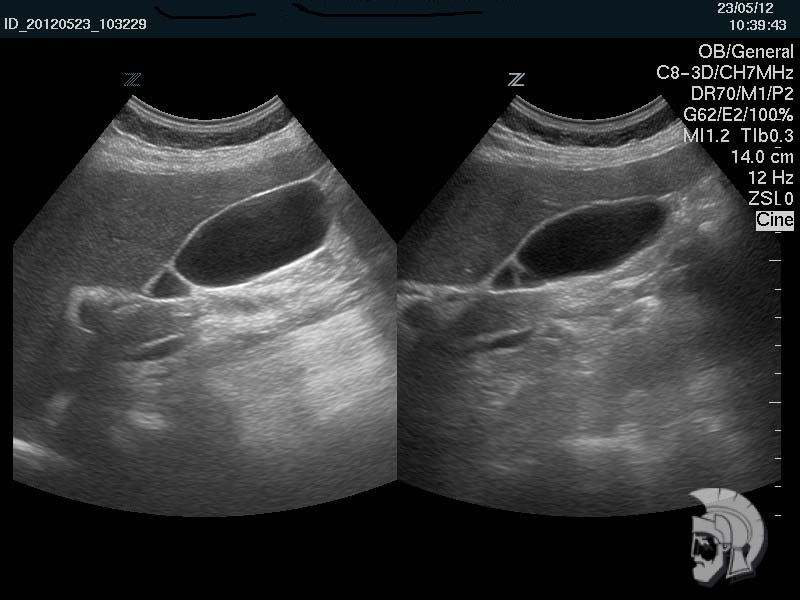

| Фото желчного пузыря. Перетяжка в нижней трети желчного пузыря мужчины 43 лет |

Обратите внимание на совершенное качество фотографий, свидетельствующих об экспертном классе наших аппаратов УЗИ!

Использование ультразвуковых аппаратов экспертного класса с режимами энергетического ДОППЛЕРа и цветового допплера позволяет врачам Курортной клиники мужского здоровья выявлять патологические изменения на ранних этапах.